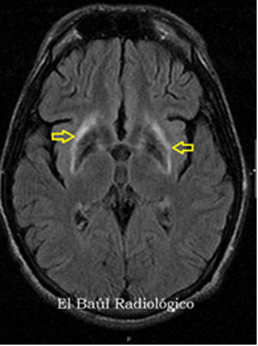

El diagnostico final fue de EW en fase presintomática.

Su depósito hepático provoca daño celular en el hepatocito que se manifiesta desde afectación hepática aislada con disfunción asintomática (habitual en niños) hasta cirrosis o insuficiencia hepática aguda grave. La afectación neurológica (más frecuente en niños mayores y adultos) por depósito de cobre en los ganglios basales cursa con síntomas extrapiramidales o cerebelosos en forma de disartria, temblor, manifestaciones psiquiátricas… y suele acompañarse de depósito de cobre en la membrana corneal de Descemet (anillo de Kayser-Fleischer). Otras alteraciones incluyen: afectación renal en forma de tubulopatía y nefrolitiasis, alteraciones esqueléticas (osteoporosis…), anemia hemolítica, Coombs negativa por depósito de cobre en los hematíes, pancreatitis y miocardiopatía.